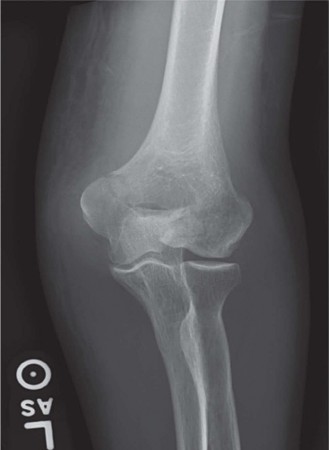

You are consulted to evaluate the right elbow of a 38-year-old female who was involved in a motor vehicle col…